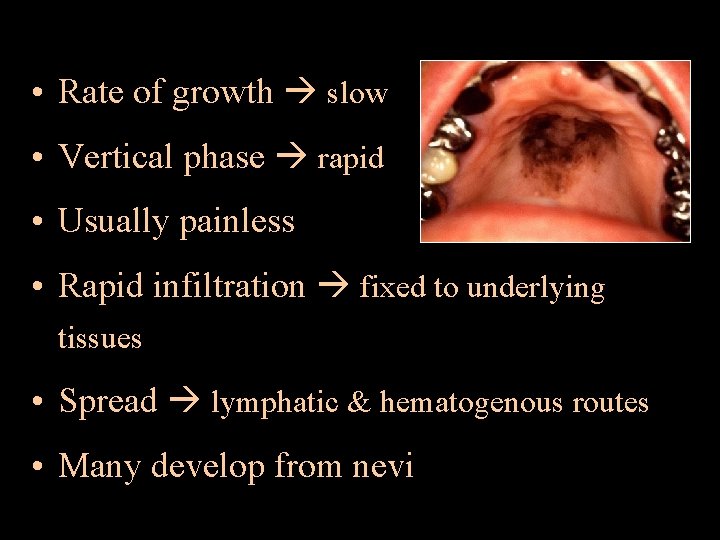

ORAL MELANOMA • Melanoma malignant tumor of nevus cells • Have a nodular component • Slightly more in males • 4 presentations – pigmented macule – pigmented nodule – large pigmented exophytic lesion – Amelanotic variety • Color mucosal pink – brown – blue – black • May ulcerate but no rolled out borders

• Rate of growth slow • Vertical phase rapid • Usually painless • Rapid infiltration fixed to underlying tissues • Spread lymphatic & hematogenous routes • Many develop from nevi

ORAL MELANOMA A – asymmetry C – color variation B – border irregularity D – diameter > 6 mm D/D: • Oral melanotic macule • Amalgam tattoo • Nevus • Focal hemosiderin deposit